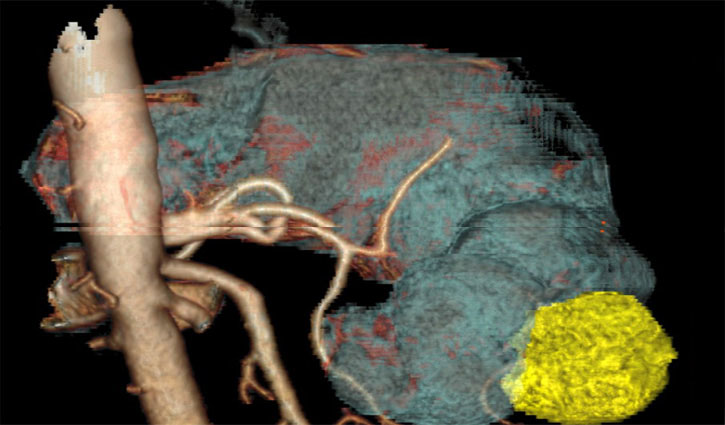

এই ছবিটি মূলত একটি পাকস্থলীর ত্রিমাত্রিক কম্পিউটেড টমোগ্রাফি (সিটি) স্ক্যানের ছবি। এখানে হলুদ অংশটি টিউমারকে প্রকাশ করছে। এই গ্যাস্ট্রোইনটেস্টাইনাল স্ট্রোমাল টিউমার বা জিআইএসটি, পরিপাকনালীর মধ্যে বিকাশ লাভ করে।